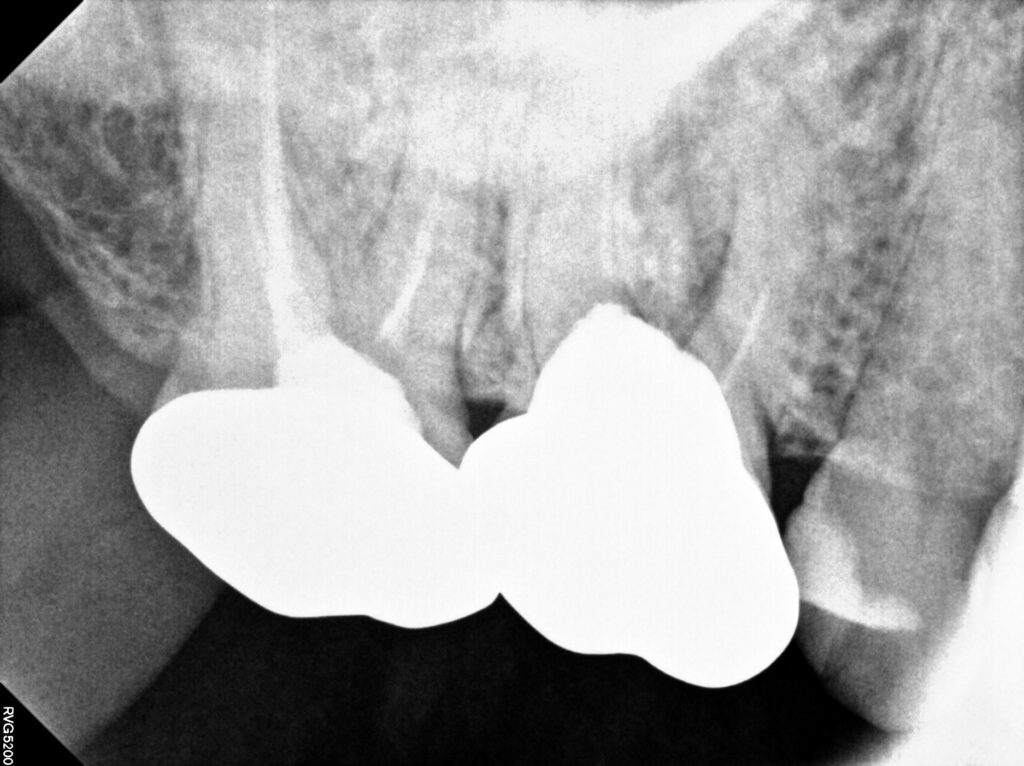

오른쪽 위 첫번째 어금니 치아 뿌리 염증으로 인해

잇몸이 부어 고름 주머니가 형성된 것을

확인할 수 있었는데요.

엑스레이나 CT 촬영에서 염증 소견이 발견되어